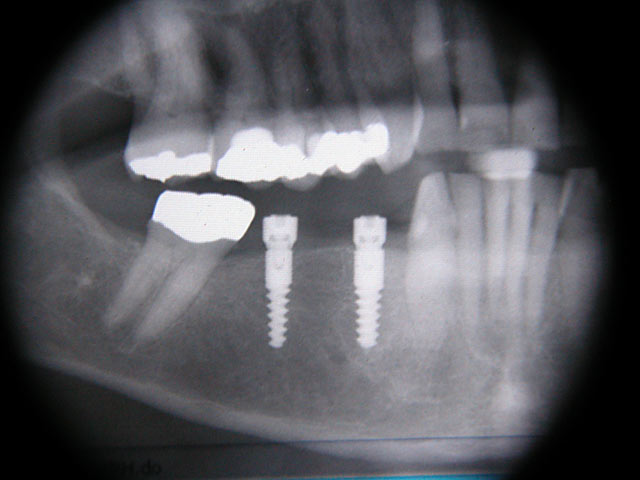

Kugelkopf-Implantation: